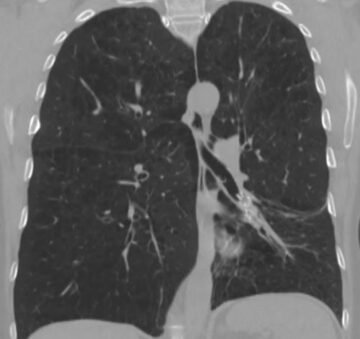

Patient with homogenous emphysema and multiple comorbidities experiencing tremendous improvement in QoL

76 y/o male with homogenous emphysema and multiple comorbidities came off oxygen after treatment (Result not typical)

Successful atelectasis of the right middle lobe with 80% fissure completeness score